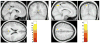

One function of spatial attention is to enable goal-directed interactions with the environment through the allocation of neural resources to motivationally relevant parts of space. Studies have shown that responses are enhanced when spatial attention is predictively biased towards locations where significant events are expected to occur. Previous studies suggest that the ability to bias attention predictively is related to posterior cingulate cortex (PCC) activation [Small, D.M., et al., 2003. The posterior cingulate and medial prefrontal cortex mediate the anticipatory allocation of spatial attention. Neuroimage 18, 633-41]. Sleep deprivation (SD) impairs selective attention and reduces PCC activity [Thomas, M., et al., 2000. Neural basis of alertness and cognitive performance impairments during sleepiness. I. Effects of 24 h of sleep deprivation on waking human regional brain activity. J. Sleep Res. 9, 335-352]. Based on these findings, we hypothesized that SD would affect PCC function and alter the ability to predictively allocate spatial attention. Seven healthy, young adults underwent functional magnetic resonance imaging (fMRI) following normal rest and 34-36 h of SD while performing a task in which attention was shifted in response to peripheral targets preceded by spatially informative (valid), misleading (invalid), or uninformative (neutral) cues. When rested, but not when sleep-deprived, subjects responded more quickly to targets that followed valid cues than those after neutral or invalid cues. Brain activity during validly cued trials with a reaction time benefit was compared to activity in trials with no benefit. PCC activation was greater during trials with a reaction time benefit following normal rest. In contrast, following SD, reaction time benefits were associated with activation in the left intraparietal sulcus, a region associated with receptivity to stimuli at unexpected locations. These changes may render sleep-deprived individuals less able to anticipate the locations of upcoming events, and more susceptible to distraction by stimuli at irrelevant locations.